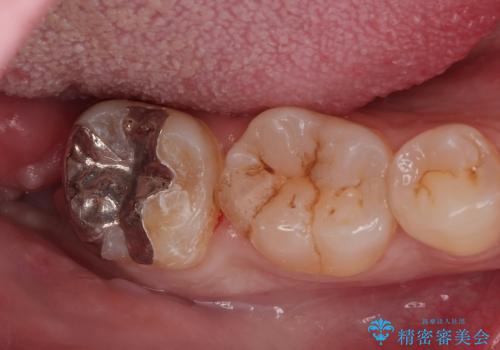

親知らず抜歯後、虫歯治療

- 親知らずが痛くて抜いて欲しいとの事で来院。CTで神経の位置を確認し、抜歯を行いました。

抜歯後、奥歯にも虫歯があったので虫歯を拡大鏡下で取りきり、メタルインレーにて治療を行いました。

しっかり麻酔を効いてるのを確認し治療を行いました。